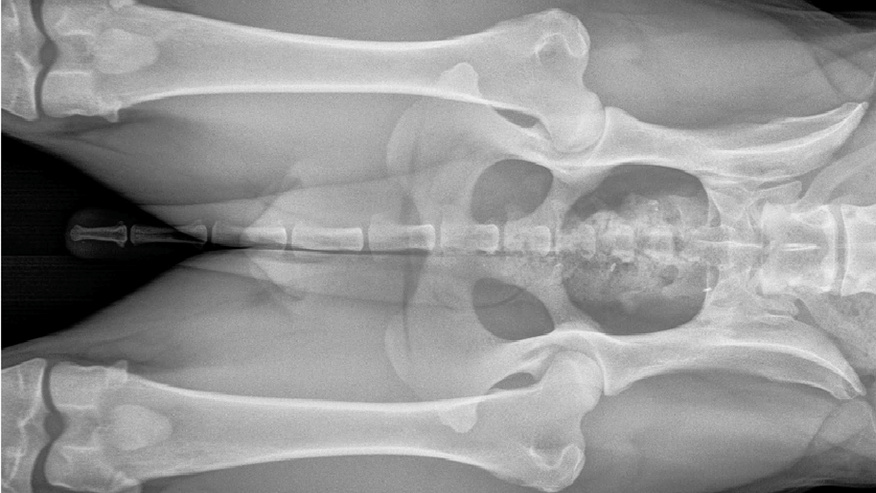

• 876x493 pet medical center OFAxray

Our hospital offers OFA x-rays for identification of hip dysplasia in dogs. OFA is the Orthopedic Foundation for Animals and is an organization that was created to aid breeders in helping reduce the incidence of hip dysplasia. Dogs must be over 2 years of age and the x-rays must be taken using general anesthesia for accurate diagnosis.... Read more